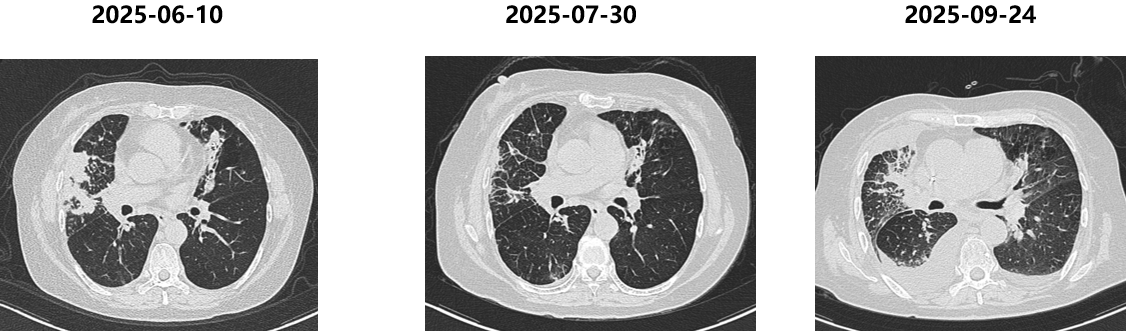

胸部CT(2025-06-10):病灶再次快速进展。

五线治疗(2025-06至今)

依据:SCLC后线治疗,DLL3靶点药物。

方案:塔拉妥单抗1mg D1,10mg D8,D15(阶梯给药)。

PFS:3个月

胸部CT(2025-09-24):病灶再次出现进展。